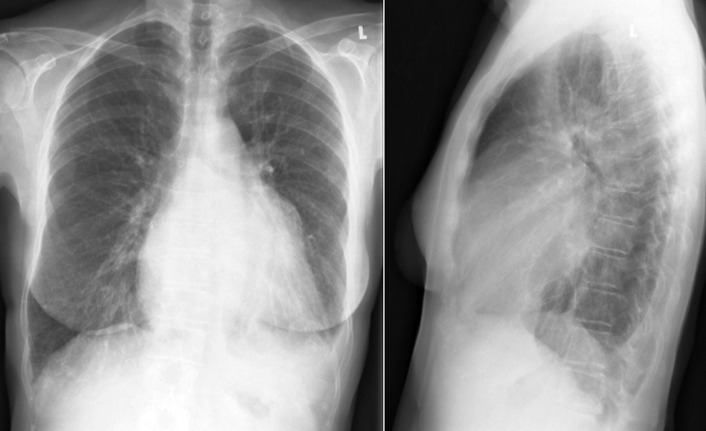

The radiographic findings of mitral stenosis ( Graphic 15-1 ; Figs. 15-1 to 15-16 ) reflect the pressure overload of the left atrium and pulmonary veins, and later of the right heart. As well, the commonly associated chronic atrial fibrillation contributes to (bi)atrial dilation. Associated rheumatic valvular lesions such as mitral regurgitation, tricuspid regurgitation, aortic insufficiency, and aortic stenosis/aortic insufficiency are common, and they alter the appearance of the heart.